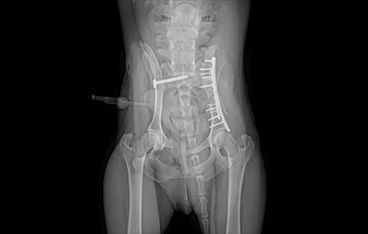

• 골반골절

• 골반골절 수술 전

골반골절 수술 후